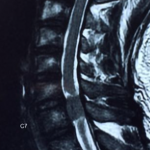

經詳細問症後,很明顯林生的問題已出現馬尾神經綜合症的病況.可能椎管內有腫瘤或腰椎嚴重椎間盤突出壓迫脊髓. 後立刻安排病人照全脊椎磁力共振,並2小時後立即幫病人看片, 果然發現病人頸椎6/7節椎管位置長了一個1.6cm腫瘤嚴重地壓著脊髓. 當日立即轉介至腦神經外科醫生,並安排當晚入院,第二日做割除頸椎管腫瘤手術. 病人術後,腳痛及痲痺,腳部乏力也徐之而改善.

頸椎6/7節椎管位置長了一個1.6cm腫瘤嚴重地壓著脊髓

頸椎6/7節椎管位置長了一個1.6cm腫瘤嚴重地壓著脊髓